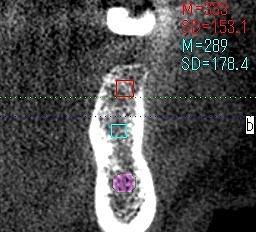

ブログ一覧|広島市安佐南区の歯科医院 ブログ一覧 トップ ブログ一覧 お知らせ スタッフブログ ブログ一覧 2018/05/10 セラミックの作成工程になります。 セレックの設計から始まります。 2018/05/10 ジルコニアのシェード合せ。 2018/05/10 インプラントは埋入診査と術中のCTデータがすべてかと思います。 2018/05/10 インプラントは埋入診査と術中のCTデータがすべてかと思います。 2018/05/09 左上のインプラント埋入。インプラント埋入難しいです。 左上6番は傾斜埋入としました。 2018/05/09 左上のインプラント埋入。インプラント埋入難しいです。 2018/05/09 左上のインプラント埋入。インプラント埋入難しいです。 2018/05/09 20年以上前に植えたインプラントもこんなに骨吸収してきます。 << 1 2 3 4 5 … 637 638 639 640 641 … 870 871 872 873 874 >> Web診療予約 初めての方へ 選ばれ続ける理由 院内設備について 歯が痛いしみる一般歯科 歯がぐらぐらする歯周病 健康な歯を保ちたい予防歯科 子供の虫歯予防をしたい小児歯科 銀歯をセラミックに審美歯科 白い歯を目指しませんか?ホワイトニング 矯正専門医がいるので安心矯正歯科 抜けた歯を補いたいインプラント・入れ歯 医院案内 スタッフ紹介 メリィハウス歯科クリニックオフィシャルホームページ ラベンダー歯科クリニックオフィシャルホームページ お知らせ・ブログ ホーム 診療科目 一般歯科 歯周病治療 予防治療 小児歯科 審美治療 ホワイトニング 矯正歯科 入れ歯・インプラント マウスピース矯正 初めての方へ 院長・スタッフ 設備紹介 医院案内・アクセス メニューを閉じる